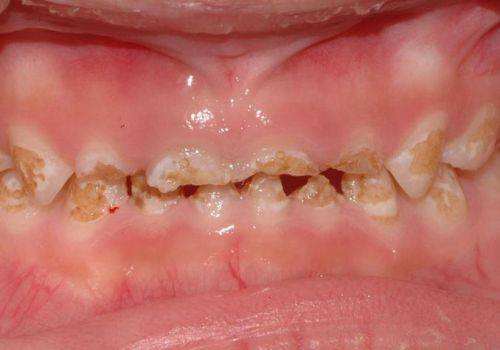

儿童齿科:接诊3-12岁儿童,开展儿童龋病治疗、早期颌面发育干预等项目,医护人员对儿童患者耐心细致,诊疗环境童趣化,降低儿童看牙的抵触情绪。